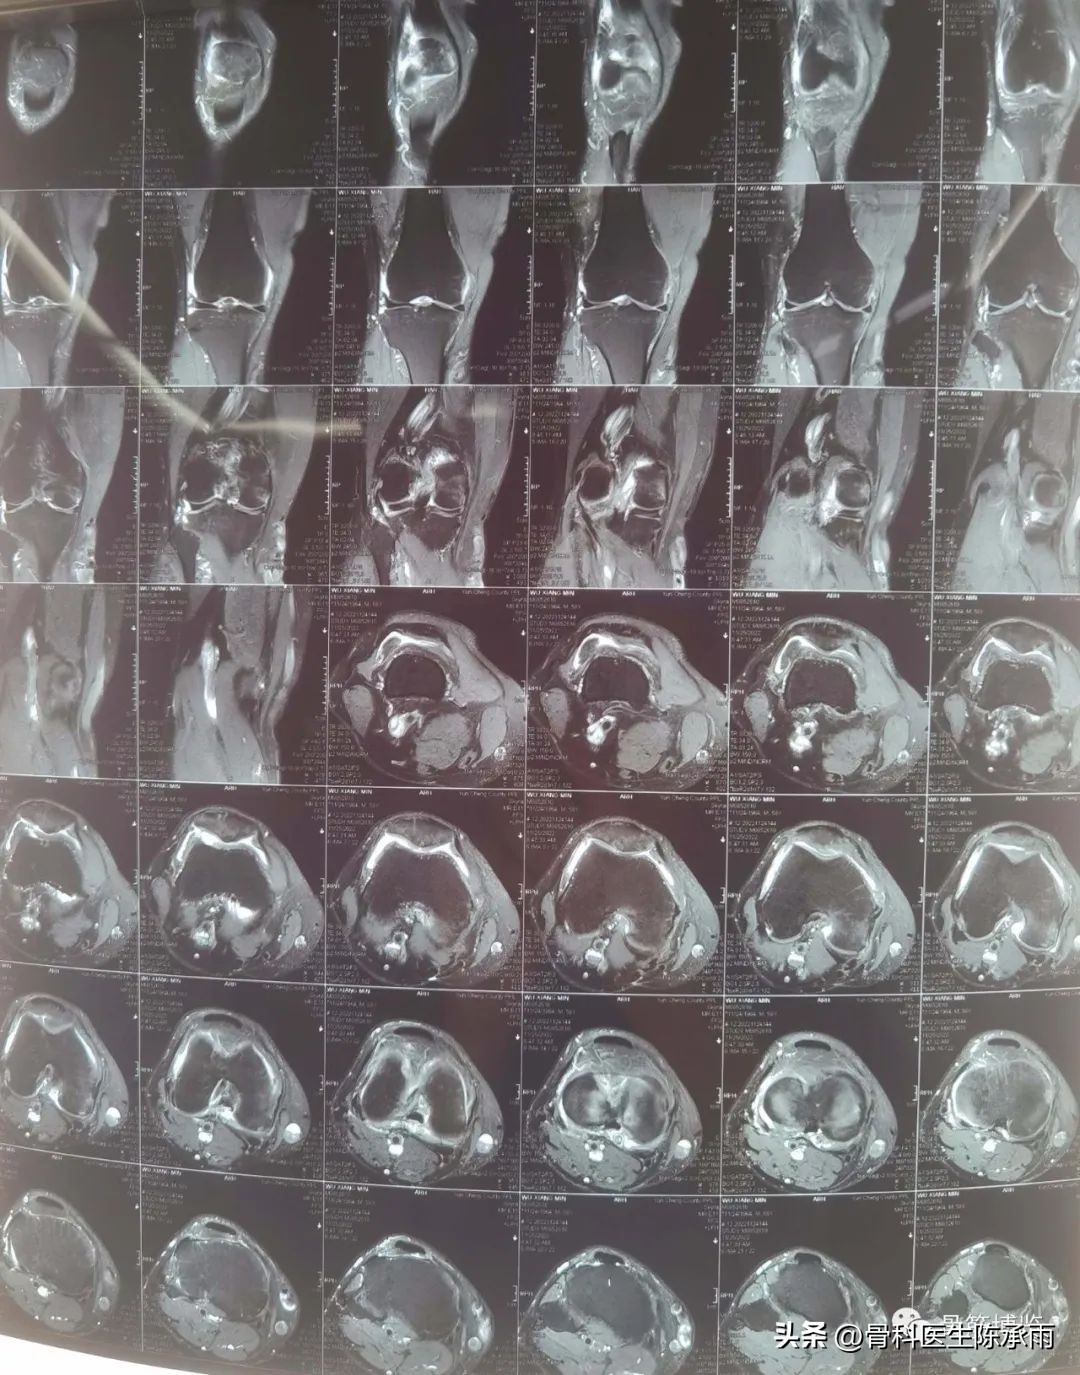

半月板损伤的类型

(一)纵裂

是指半月板的裂口与半月板纵轴相平行的撕裂。可以是垂直的,也可以是斜行的;可以是全层的,也可以是非全层的。常见于外伤直接的撞击或是随着关节囊的撕裂而形成。裂口为垂直方向的,与半月板边缘平行。其中又分为完全性的纵裂和不完全性的纵裂。完全性的(即全层的)纵裂,在裂口较大时,其内侧游离缘部分可以脱位于髁间窝,即形成典型的提篮状或者桶柄状撕裂。这种损伤容易导致关节绞锁,使关节屈伸受限。当撕裂时间较短,内侧的游离部分较完整,尚能较好地复位时,可以施行半月板缝合术,特别是接近滑膜缘的纵裂,缝合的效果较好,成功率较高。如果是不完全性的(即非全层的)纵裂则往往合并有层裂或斜裂,探查时应予注意。

(二)水平裂

是指半月板的裂口与半月板表面相平行的撕裂。在成人及上年纪的人中较常见。多见于内侧半月板的体后部和外侧半月板的体部。大部分活瓣状撕裂和复合裂即由层裂发展而来。盘状软骨损伤中更为多见,有的可向上或向下通向关节,有的则仅为单纯的层裂。

(三)斜裂

是指由内侧游离缘斜行走向半月板体部的全层撕裂。斜向后角方向的称为后斜裂,反之则称为前斜裂。

(四)活瓣状裂

另外有一部分非全层的斜裂形成舌状,或在股骨面上,或在胫骨面上,或向前反折或向后反折形成活瓣状撕裂。

(五)横裂

是指裂口的方向与半月板纵轴相垂直,呈放射状,从游离缘裂向滑膜缘,大部分是全层的垂直撕裂。

(六)复合裂

是指上述两种以上的撕裂同时存在的一种损伤类型。在半月板的慢性损伤中较为常见。多见于老年人或半月板损伤病史较长的病人。它们大部分是由于慢性的、长时间的、多次损伤而形成,而并非一次明确的损伤所致。特别是股骨髁半月板区和胫骨平台软骨严重损伤的病人,这种情况更为多见。至于它们之间的因果关系,并不清楚。是先有关节软骨损伤,还是先出现半月板撕裂,还有待进一步研究。

(七)退行性变性撕裂

因为这种撕裂表现为明显的不规则性,往往见于老年骨性关节炎的病人。我们认为它不是一种单纯的损伤,而是由于关节软骨退行性改变后,股骨髁的半月板区骨及软骨与相对应的胫骨平台表面软骨间,长期反复的磨损所致。在有的病人,甚至镜下也不能观察到完整的半月板形态,仅可见残留的参差不齐的半月板边缘。而这时的关节软骨已大部分剥脱,仅剩淡红色的骨床以及表面的部分软骨岛。